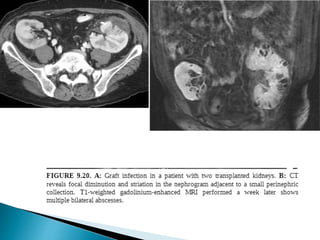

 Unusual complication.

 First 2 weeks of transplant surgery.

 Predisposing causes :- Acute rejection. ATN, vascular occlusion.

 Imaging

 Graft recipient>>> donor…  Incidence and severity rely on 1. dose of immunotherapy 2. DM 3. Co-existant graft dysfunction.  Organisms:- Gram negative pathogens/CMV/HSV.